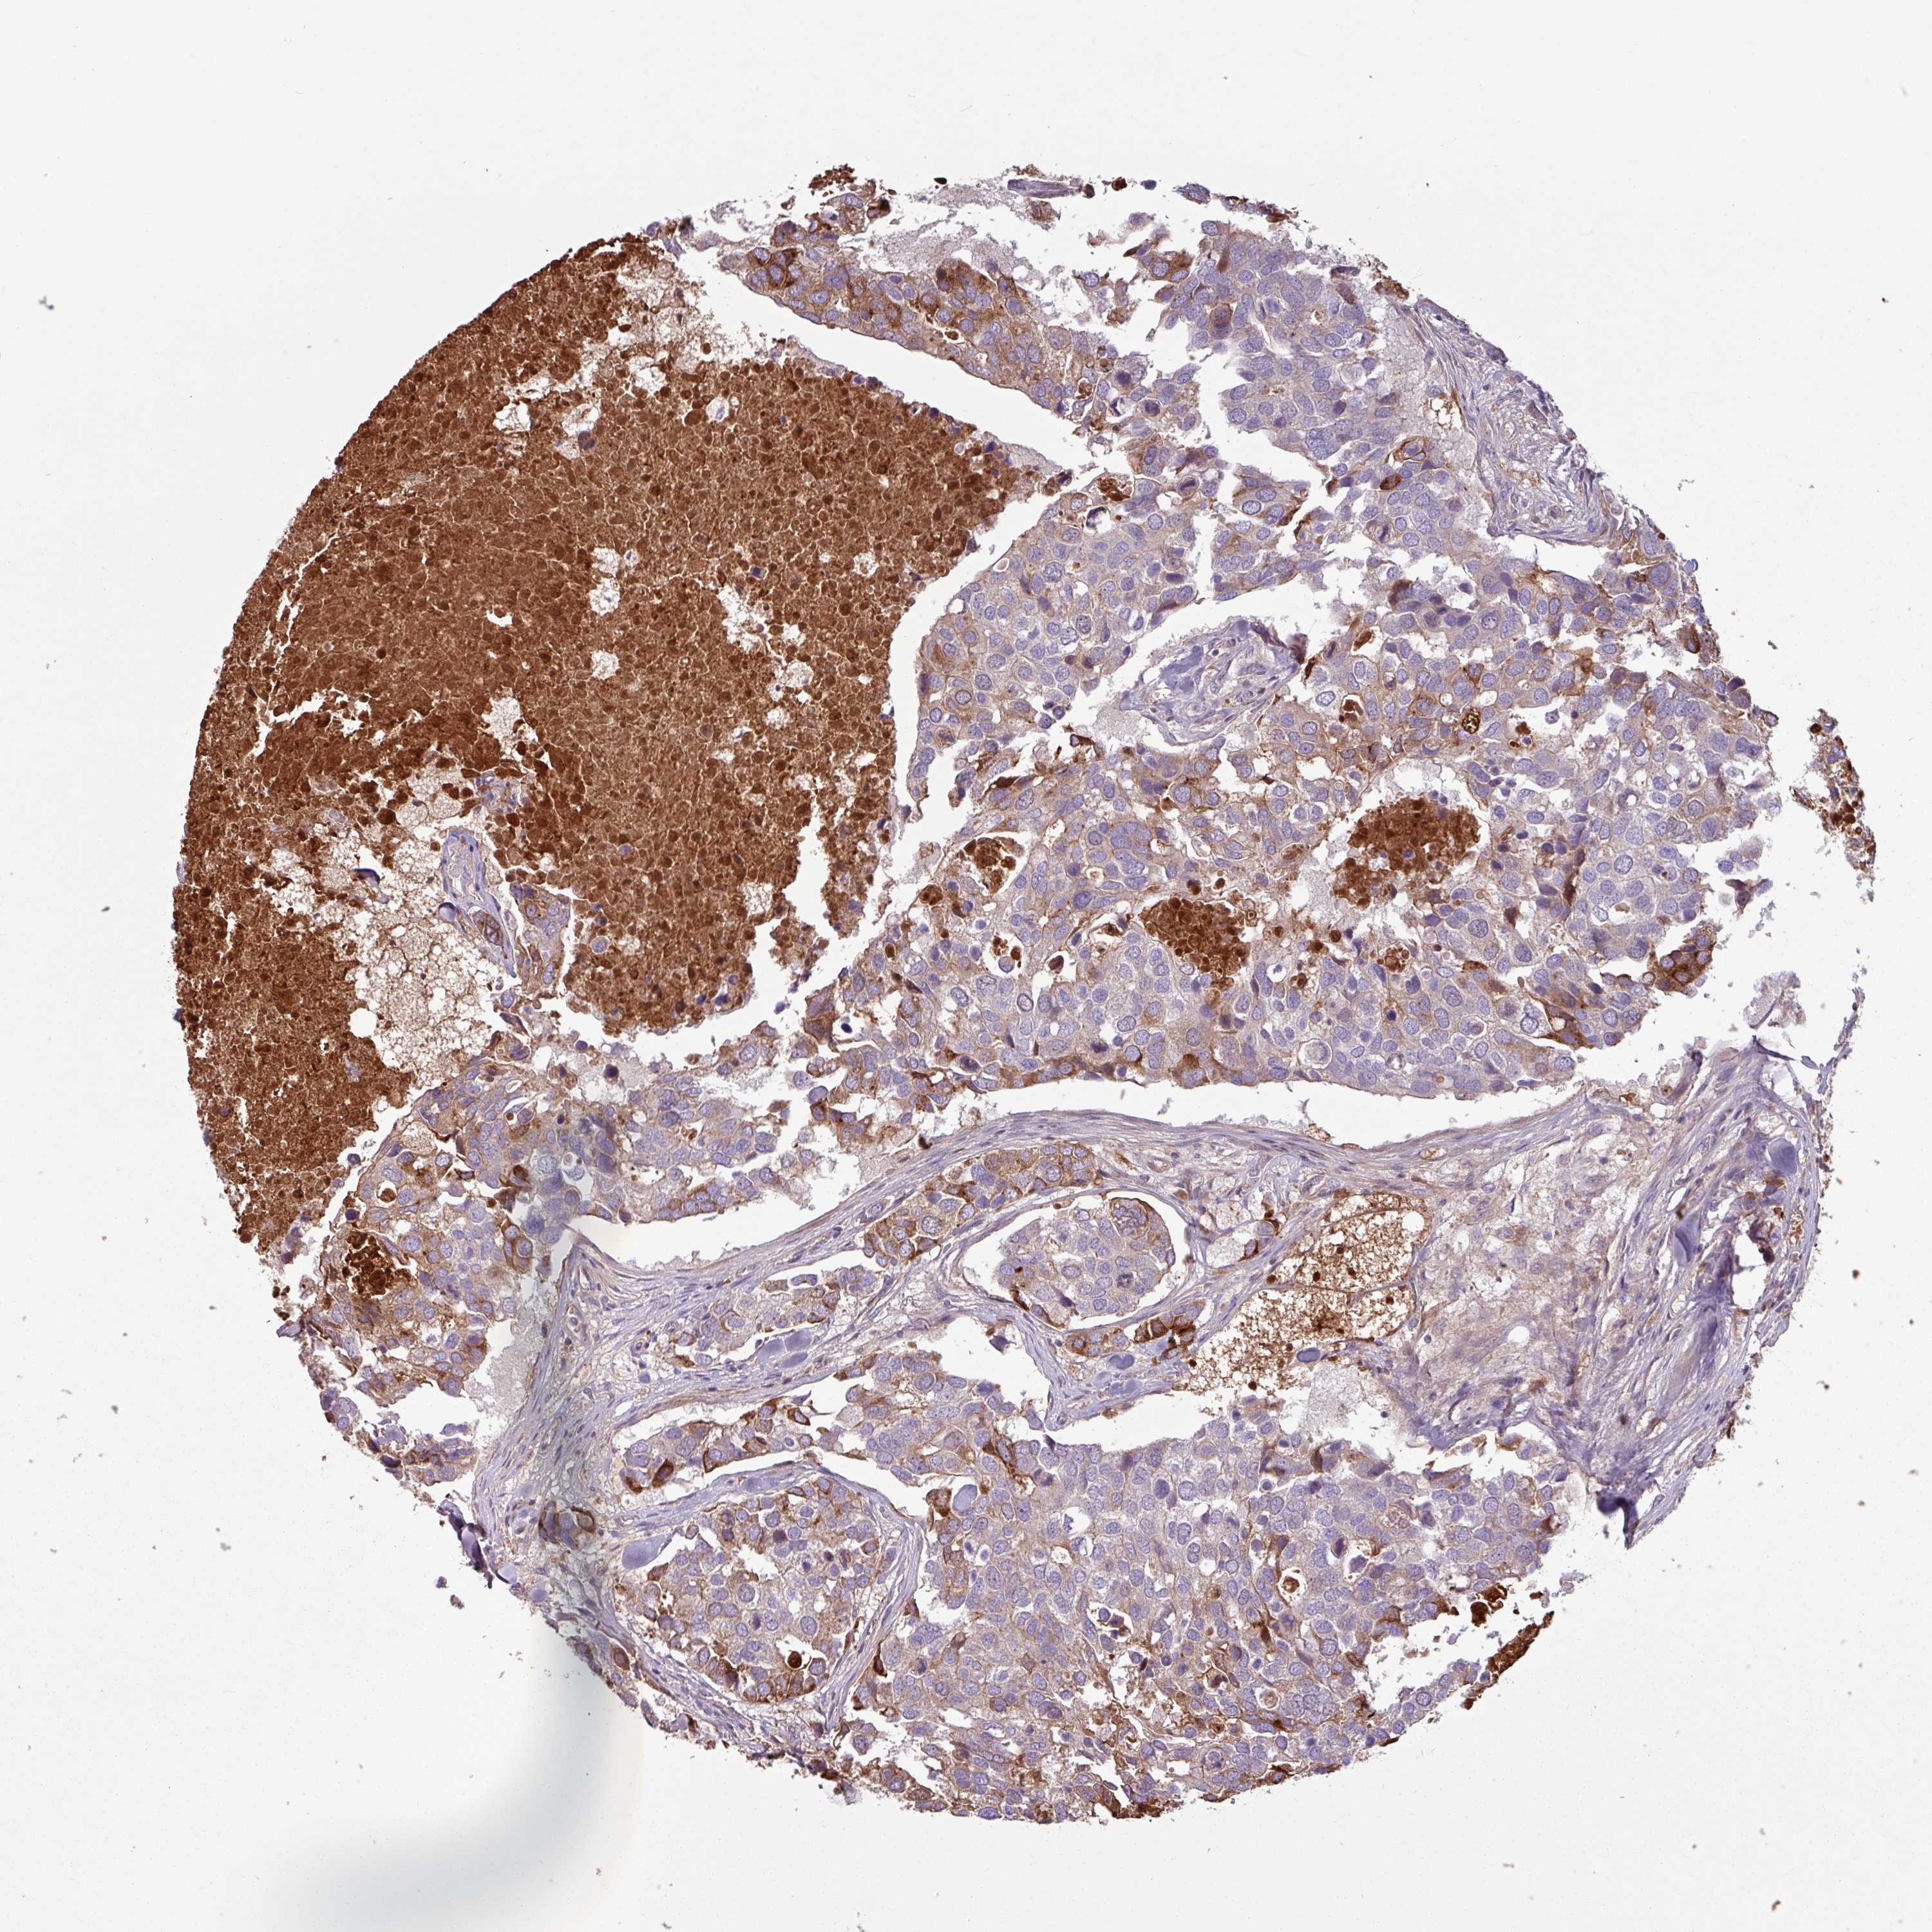

BRCA TCGA BRCA VALIDATION PROTEIN EXPRESSION

ANTIBODIES

AND

VALIDATION